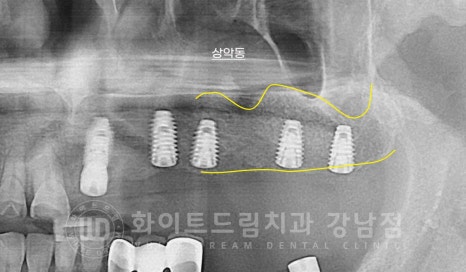

▲ 더 이상 사용이 불가능한 상악 브릿지와 제거된 하악 임플란트입니다.

환자분은 경상남도에서 내원을 해주시는 분이시기에

내원 횟수를 줄이기 위해 내원 당일 보철과 임플란트를 제거한 후 바로 임플란트 식립을 진행합니다.

환자분은 상악 모자란 잇몸뼈 부위를 다시 형성할 수 있도록

상악동 거상술, lateral도 당일 함께 시술을 받으셨습니다.

대량의 뼈이식 재가 들어갔기 때문에 최대한 임플란트가 자극을 받지 않도록

임플란트를 잇몸뼈 안에 식립한 상태로 봉합하게 됩니다. (1차 수술만 진행)

수술일자 : 23.08.19